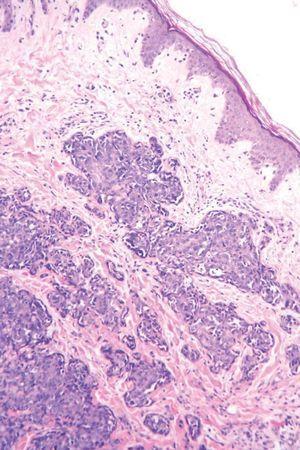

Varón de 42 años, intervenido a los 10 años de una lesión en la ingle derecha que el paciente definió como «lipoma» (no aportó informe anatomopatológico). A partir de dicha intervención desarrolló un aumento del diámetro de la extremidad inferior derecha (homolateral a la extirpación del lipoma), que se extendió al muslo y los genitales, siendo diagnosticado de linfedema secundario de miembro inferior derecho. Años después apareció una lesión eritematosa extensa y mal definida que abarcaba la mayor parte del territorio del linfedema, respetando pequeñas zonas como la raíz del muslo (figs. 2 y 3). En el diagnóstico histológico, la tinción de hematoxilina-eosina (fig. 4) mostraba pocas luces vasculares por tratarse de un angiosarcoma poco diferenciado. Por esta razón, el diagnóstico fue confirmado por las técnicas inmunohistoquímicas: citoqueratina negativa (que tiñe las células epiteliales, y por tanto esta neoplasia no está constituida por células derivadas del epitelio), vimentina positiva (que tiñe células tumorales) y CD34 positivo (este último marcador es diagnóstico, pues es específico del endotelio vascular del que deriva esta neoplasia) (fig. 5). Se realizó estudio de extensión (tomografía axial computarizada [TAC] toracoabdominal y resonancia magnética [RM] de miembro inferior derecho) que resultó negativo. Se inició un tratamiento con ifosfamida más adriamicina, recibiendo un total de cuatro ciclos. En la respuesta clínica se observó una disminución del edema y eritema. Se trató posteriormente con adriamicina liposomal con nula respuesta y desarrollando complicaciones como fenómenos isquémicos distales y sobreinfección. Debido a la mala evolución se decidió la amputación del miembro con desarticulación de la cadera e injerto en muñón. Actualmente se ha confirmado la progresión de la enfermedad con afectación cutánea, localizada en el flanco izquierdo y está recibiendo quimioterapia de segunda línea.

Fig. 4.--Tinción hematoxilina-eosina. Se observan pocas luces vasculares (poco diferenciado).